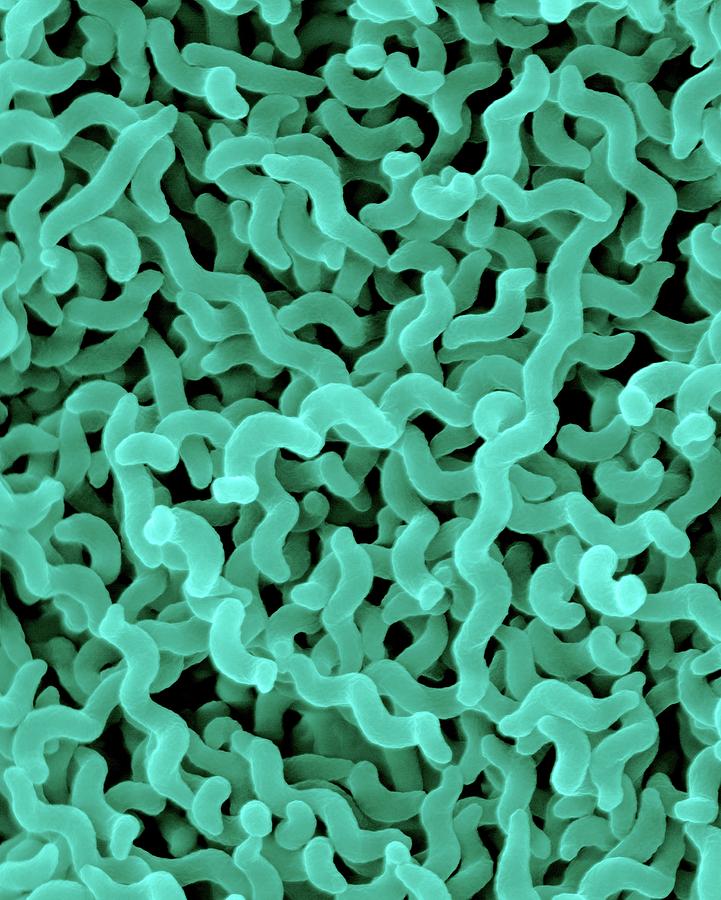

Кампилобактер фетус: патогенез и инфекции

/evrimagaci.org%2Fpublic%2Fcontent_media%2Fb099374a4578fc241a0555a594831216.jpeg)